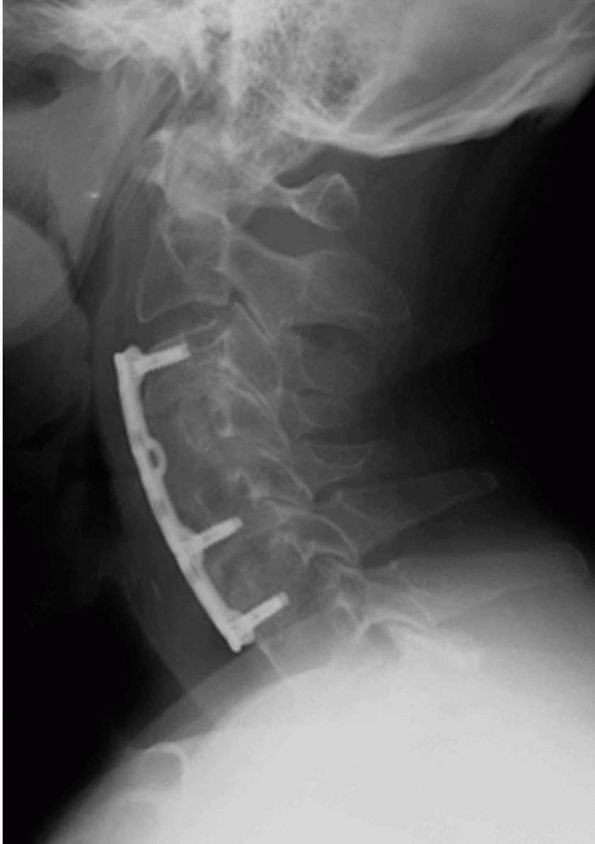

![]() |

FIGURE 11-8.

A lateral radiograph demonstrating an anterior cervical fusion with plating done in conjunction with a corpectomy and C5-C6 diskectomy used to decompress the spinal cord in a patient with cervical myelopathy. |

progressive neurologic deficit with a radiculopathy. Options are anterior or posterior decompression with or without fusion (Figure 11-8),

depending on location and type of compressive pathology. Cervical

myelopathy resulting from degenerative spondylosis or disc herniation

is typically treated surgically. Patients presenting with cervical

myelopathy seldom improve with nonoperative management and roughly

one-third will continue to deteriorate, sometimes suddenly with

hyperextension. The intent of surgical decompression in myelopathy

patients is to prevent progression with neurological improvement being

secondary and unpredictable. Because one cannot foresee those patients

that will deteriorate while being treated nonoperatively, surgical

management is favored. Options are anterior decompression via

corpectomy, diskectomy, and fusion versus posterior complete

laminectomy and decompression. In the case of multilevel disease (3 or

more levels), open door hinged laminoplasty, in which the lamina is cut

on one side and hinged on the other side to create a flap-type opening

and thus expand the spinal canal, has been gaining favor (Figure 11-9).